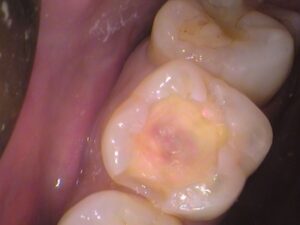

虫歯を丁寧に削り取っていきます。

その都度、虫歯を染め出して虫歯の残っている所を確認します。

染まっている箇所がだいぶなくなってきました。

うっすら色が残っている所も丁寧に取っていきます。

綺麗に虫歯が取れました。